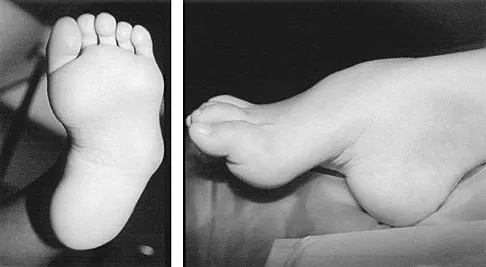

Question 58

Figures 43a and 43b show the clinical photographs of a 4-month-old child with bilateral popliteal pterygium. The fixed knee contractures measure 100 degrees bilaterally. What future treatment is most likely to successfully correct this deformity?

Explanation